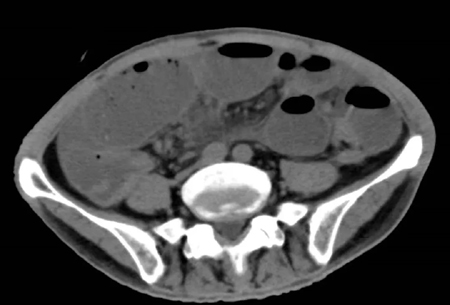

2022年5月的一个凌晨,一位93岁的老奶奶因为腹胀伴呕吐被送到了新龙泽院区急诊科,经过问诊和初步查体后,接诊医生考虑患者存在肠梗阻,立即为患者申请了急诊腹部CT检查,结果显示患者的升结肠存在一个巨大的肿物堵塞了肠腔。在给予补液和胃肠减压的同时,普外科立即对患者的病情进行了紧急评估和讨论。肿瘤导致患者出现肠梗阻,手术是唯一的解决方案,但患者高龄且身体非常瘦弱,围手术期发生肺部感染、心脑血管事件等并发症的概率非常高。普外科高鹏骥主任医师制定了急诊实施腹腔镜下右半结肠切除的手术方案,并在麻醉科和手术室医护团队的密切配合下顺利完成了手术。